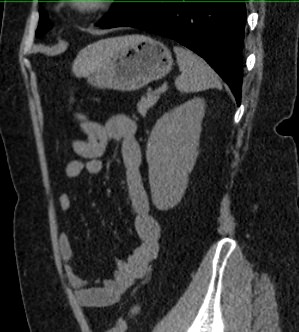

Мультиспиральная компьютерная томография (МСКТ) брюшной полости относится к современным лучевым методам исследования, с помощью которого можно оценить состояние органов брюшной полости (печени, желчного пузыря, поджелудочной железы, селезенки), прилегающих к ним кровеносных сосудов и лимфатических узлов.

С помощью мультиспиральной компьютерной томографии проводятся послойные рентгеновские снимки исследуемой области с толщиной среза от 0,5 мм. В нашей клинике исследование выполняется на компьютерном томографе экспертного класса TOSHIBA AQUILION CXL, который оснащен 128 детекторами, позволяющими получать за несколько секунд снимки брюшной полости с высокой точностью. Большое количество детекторов позволяет получить точные данные, при этом сократить время исследования и сделать минимальной лучевую нагрузку на пациента. Кроме того, инновационные технологии аппарата дают возможность сформировать объемную модель органа и окружающих структур, что также способствует проведению точной и достоверной диагностики.

При подозрении на опухоли, воспалительные процессы, гнойные очаги назначается КТ брюшной полости с внутривенным болюсным контрастированием. Для этого пациенту внутривенно вводится рентгеноконтрастное вещество на основе йода. Благодаря усиленному кровоснабжению препарат накапливается в структуре патологических образований и помогает врачу-рентгенологу выявить изменения в структуре внутренних органов.

Метод контрастирования помогает максимально точно выявить очаг патологии уже на начальной стадии, а также установить его локализацию, точные размеры, форму и особенности кровоснабжения.